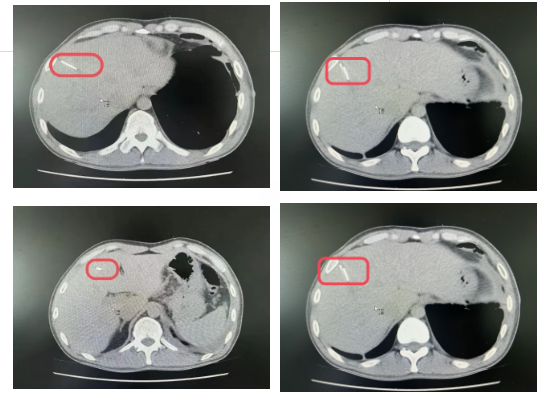

术中,面对肝脏与周围腹壁严重粘连的挑战,刘宏宇医生凭借精湛的技术,依据术前精确的影像学定位,于粘连边缘约2.0cm处巧妙使用超声刀切开肝脏包膜,最终完整无损地取出了四枚长约2.5-3.0cm,直径约2.0mm的金属异物。在手术麻醉科医护团队与肝胆外科医师团队的紧密配合下,手术顺利告成,患者术后安全返回病房,恢复状况良好,现已康复出院。此次手术的成功,不仅体现了兴安盟人民医院肝胆外科团队的高超医术和精湛技艺,也彰显了医院在多学科协作、紧急救治方面的强大实力。

腹部切口图像